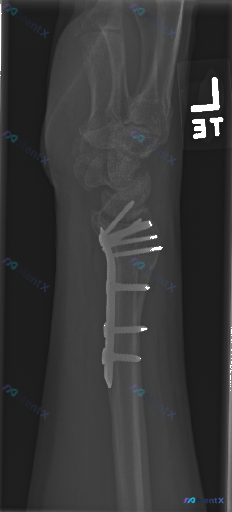

左侧桡骨远端骨折,已行掌侧锁定加压钢板+螺钉内固定术。

- 内固定:钢板位于桡骨远端掌侧,多枚螺钉在位,位置良好,未见明显松动、断裂或移位;螺钉末端在关节面下方,未明显进入关节腔。

- 骨折局部:桡骨远端陈旧性骨折线影模糊,但骨痂形成尚不明显;骨折断端对位尚可;桡骨干、尺骨其余骨皮质连续。

- 关节与序列:近排腕骨、头状骨等排列基本维持;桡骨远端掌倾角在钢板固定下基本正常;桡腕关节、腕骨间关节、下尺桡关节间隙清晰,对位尚可。

- 其他:腕关节周围软组织轻度肿胀,脂肪垫层次尚可;未见明显皮下气肿、异常钙化或其他异物;桡骨远端局部骨密度稍增高(考虑骨折愈合反应),未见广泛骨质疏松或溶骨性破坏。